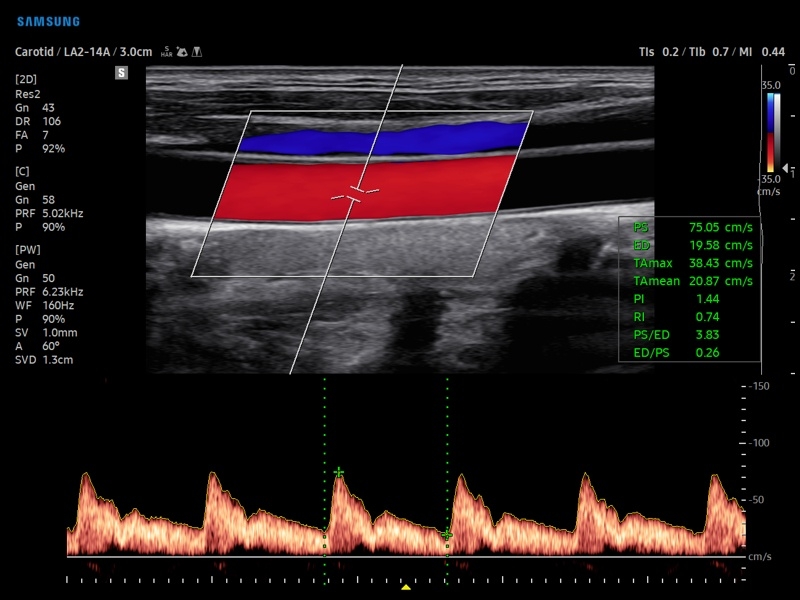

• Модуль AutoIMT - автоматическое вычисление комплекса интима-медиа общей сонной артерии (Intima Media Thickness). Данная оценка имеет большое значение для ранней диагностики атеросклероза и оценки риска развития инсульта и инфаркта миокарда.

• Модуль 2D Arterial Analysis программа, позволяющая автоматически провести анализ толщины и эластичности стенок разных участков сонной артерии, с выведением результатов в графической форме в движении (кинопетле) аналогично программе Strain для эхокардиографии.

• Сонные артерии:автоматическая, полуавтоматическая, ручная трассировка доплеровского спектра; ПСС, КДС, %СтПлощ, %Ст Диам, площадь сосуда, диаметр сосуда, средняя толщина интимы, объемный кровоток.

• Артерии верхних конечностей:автоматическая, полуавтоматическая, ручная трассировка доплеровского спектра; ПСС, КДС, %СтПлощ, %Ст Диам, площадь сосуда, диаметр сосуда, объемный кровоток.

• Артерии нижних конечностей:автоматическая, полуавтоматическая, ручная трассировка доплеровского спектра; ПСС, КДС, %СтПлощ, %Ст Диам, площадь сосуда, диаметр сосуда, объемный кровоток.

• Вены нижних конечностей:автоматическая, полуавтоматическая, ручная трассировка доплеровского спектра; максимальная скорость, диаметр сосуда.

• Сосуды брюшной полости:автоматическая, полуавтоматическая, ручная трассировка доплеровского спектра; ПСС, КДС, %СтПлощ, %Ст Диам, площадь сосуда, диаметр сосуда, объемный кровоток.